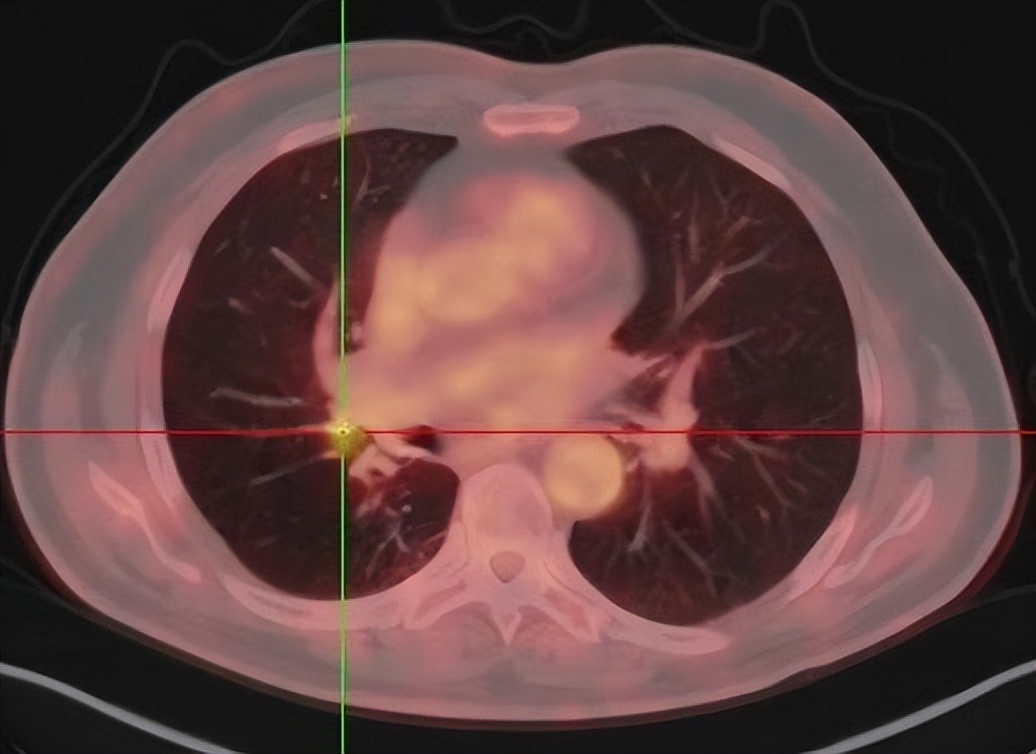

患者2018年2月出现咳嗽加重,2018-03-07 PET/CT检查报告:1、右肺癌术后,右肺门旁软组织伴肺门淋巴结FDG代谢异常增高灶(SUVmax=4.76),术后转移可能,建议随访。右残肺少许炎症。双肺气肿。2、脂肪肝,肝囊肿。3、右侧肾上腺腺瘤可能。4、前列腺增生。5、甲状腺术后。6、余全身(包括脑)PET显像未见FDG代谢明显异常增高灶。考虑右肺腺癌术后复发及肺门转移。

(2018年3月7日PET/CT提示右肺门旁软组织伴肺门淋巴结FDG代谢异常增高)